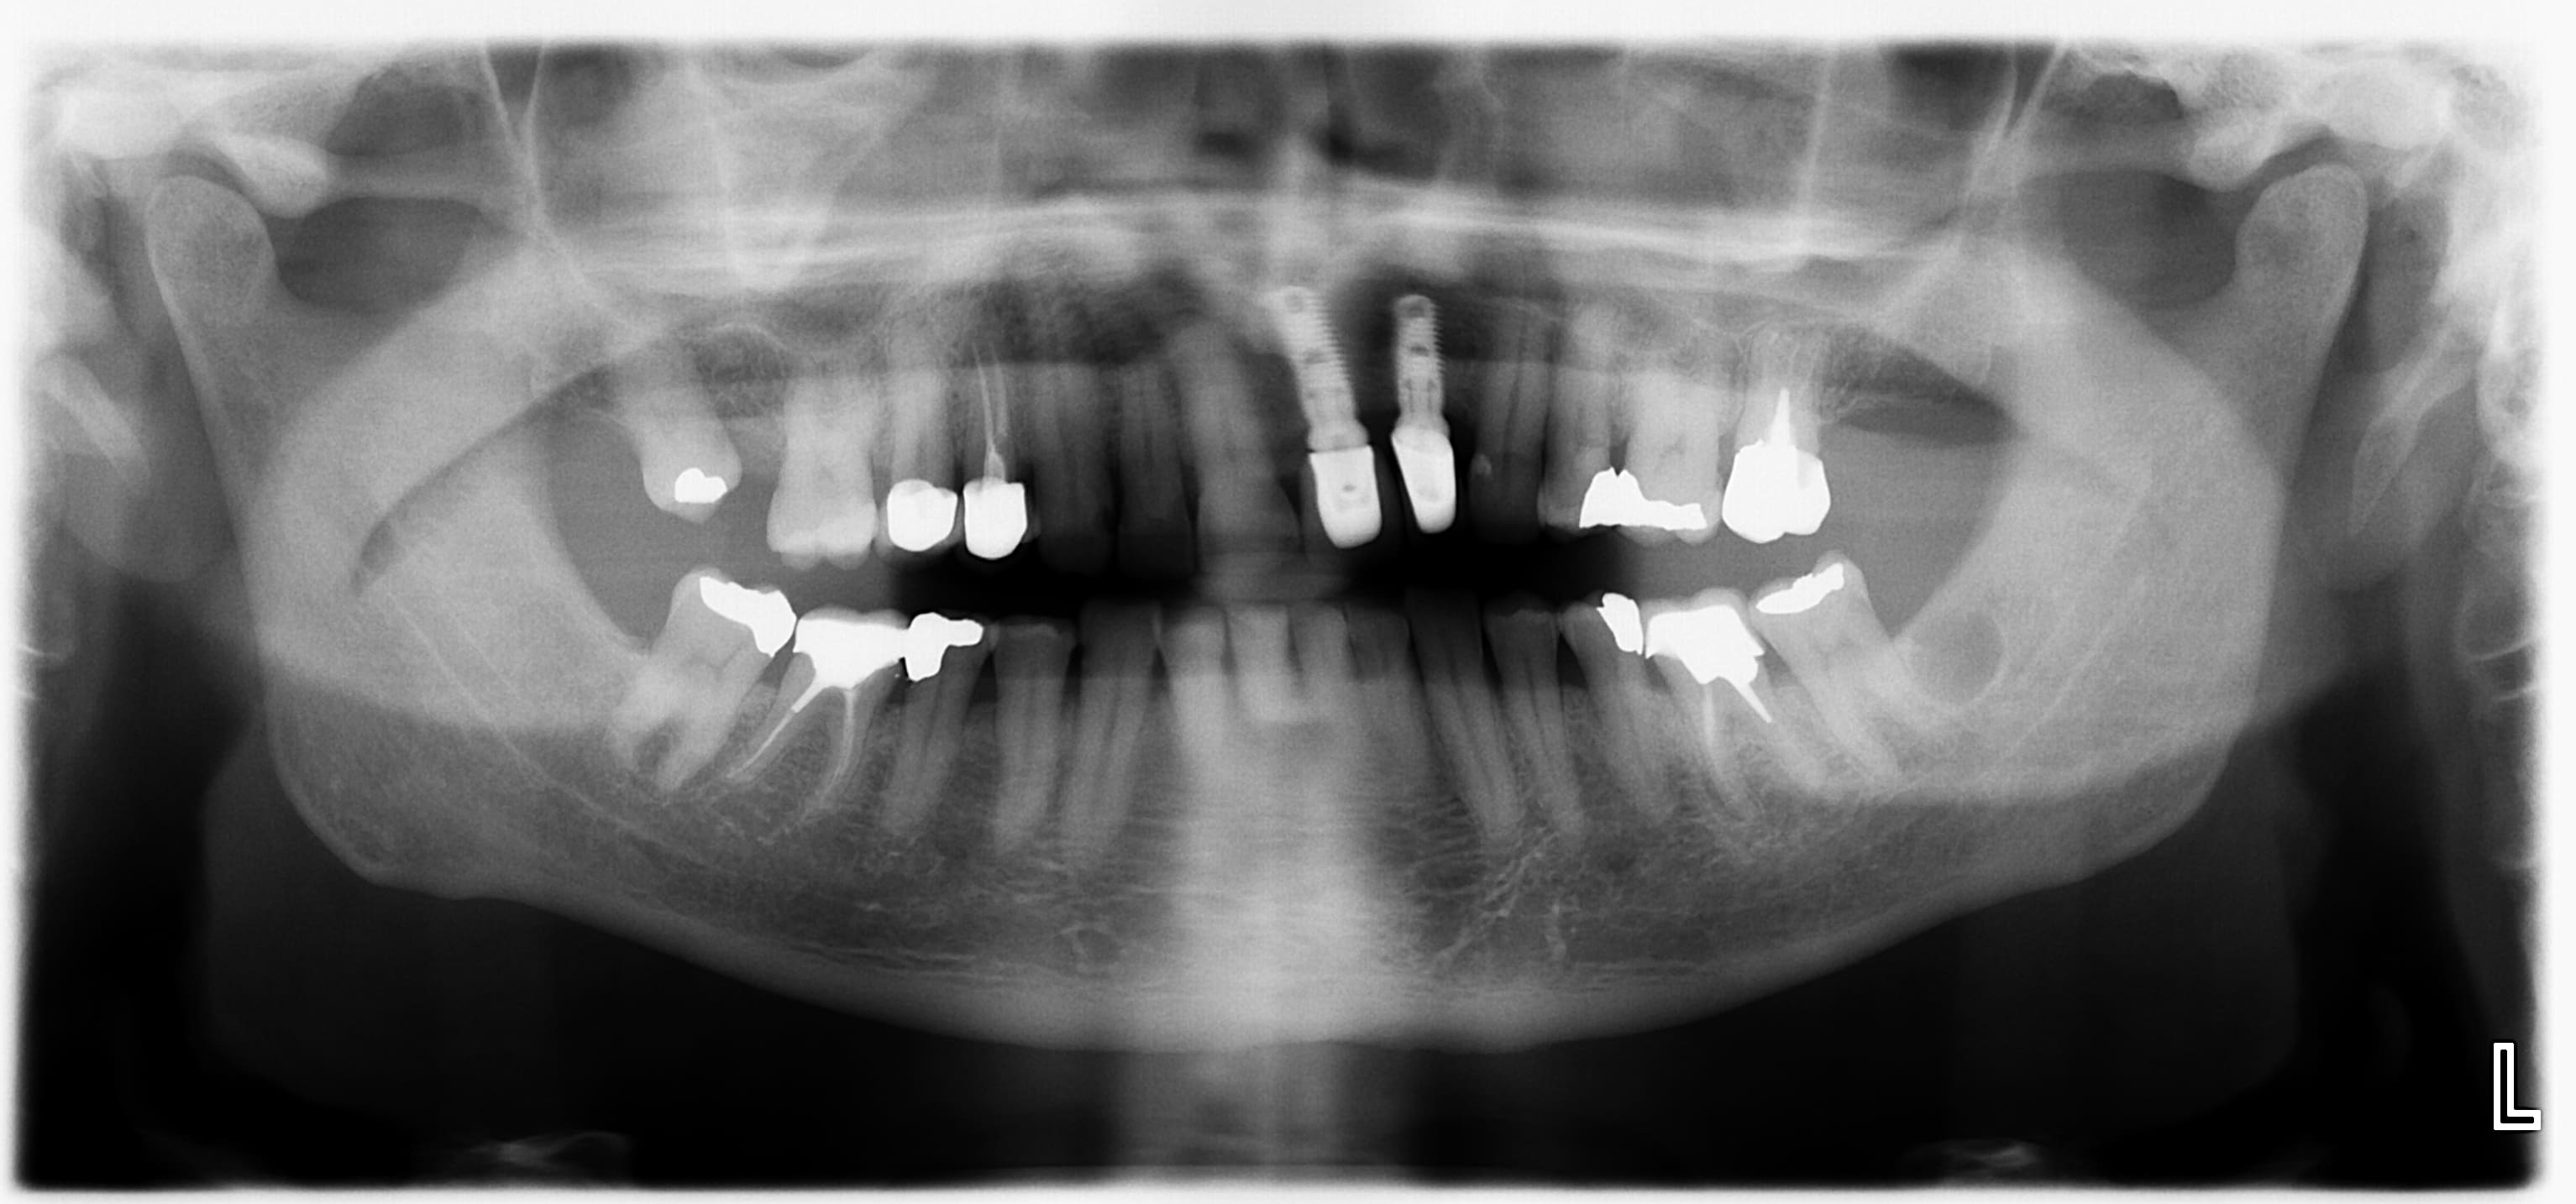

-la seconde, patient 70 ans, non fumeur, traitement psy médicamenteux, non fumeur. La lésion radioclaire en distal de 37 était absente sur la précédente pano datant de 8 ans. J'envoie pour exérèse/biopsie?

La 2 j’enverrai aussi pour biopsie exérèse faut pas le laisser comme ça , même si ça à l’air bien bénin vu la forme et le liseré osseux. Ça pourrait être un kyste résiduel d’une ancienne avulsion ou divers tumeur bénigne de l’os.

Même avis, les limites sont nettes, rien de visible en bouche.

La sagesse est absente depuis bien avant que je le connaisse, et il n'y avait rien en 2016.

Des anciennes radios pour le second cas en particulier avec la pose des implants???????

Oui, pano précédente en 2016, il n'y avait rien.

Après vérif, la 38 (et 28 48) a été extraite en 2013 chez le maxillo-facial.

Ca fait longuet tout de même pour qu'il y ait un lien.

Ca ressemble quand même sacrément à un kyste résiduel radiologiquement. Aucun symptôme? Ca ne me choque pas qu'un peu de tissu résiduel ait mis plus de 3 ans avant de faire une lésion osseuse visible à la pano.

De toute façon adressé pour exérèse et biopsie (ou carrément le faire toi même).